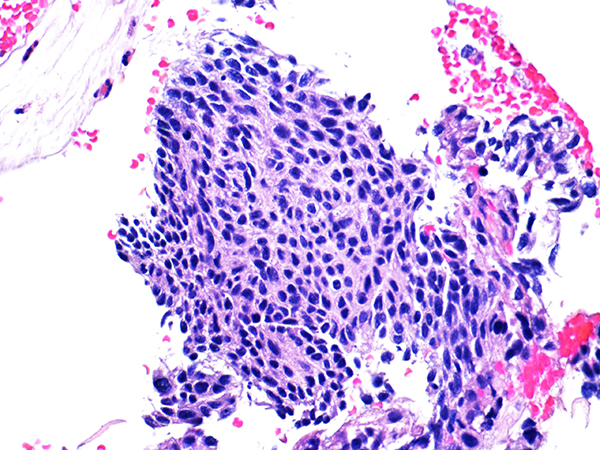

Case 1

Area 2 - Soft Bx CIN 2

40x - High Power